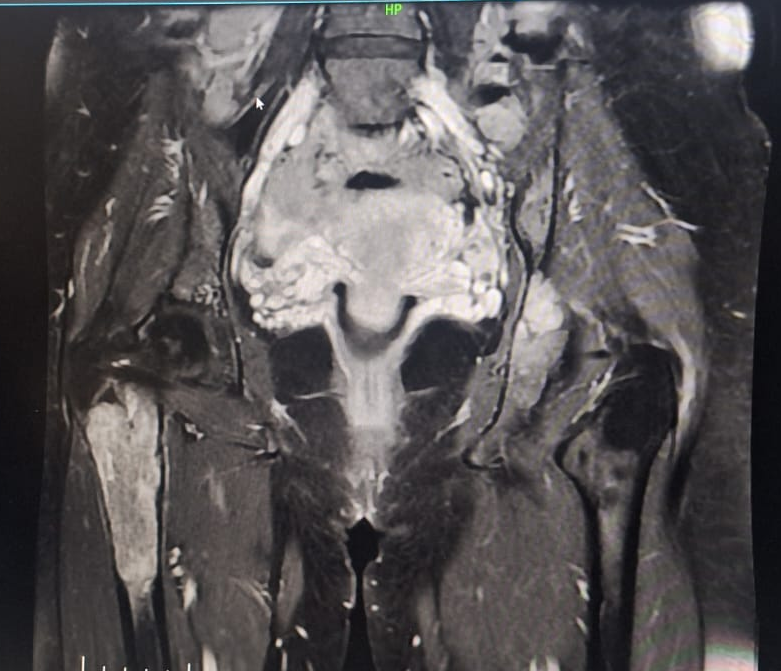

In 2022, the patient presented with progressive pain and restricted range of motion of the right hip following minor trauma. She was re-evaluated clinically and imaging was done. Radiographs (Fig 4 ) and MRI (Fig 5) revealed an expansile lytic lesion of the right proximal femur consistent with intraosseous hemangioma. Due to risk of pathological fracture we planned for fixation of right proximal femur. She underwent right proximal femoral bone excision biopsy and dynamic hip screw fixation with iliac–fibular strut bone grafting (Fig 6). Post-operative period was uneventful. Started partial weight bearing after 45 days followed by full weight bearing by 90 days. Very good radiological incorporation of graft noted and fixation was stable radiologically (Fig 7). Histopathology report suggestive of benign bone hemangiomatous tissue without any features of malignancy (Fig 8).

MRI of the proximal femur showed characteristic high-flow vascular channels consistent with intraosseous hemangioma (Fig 5).

Figure 5